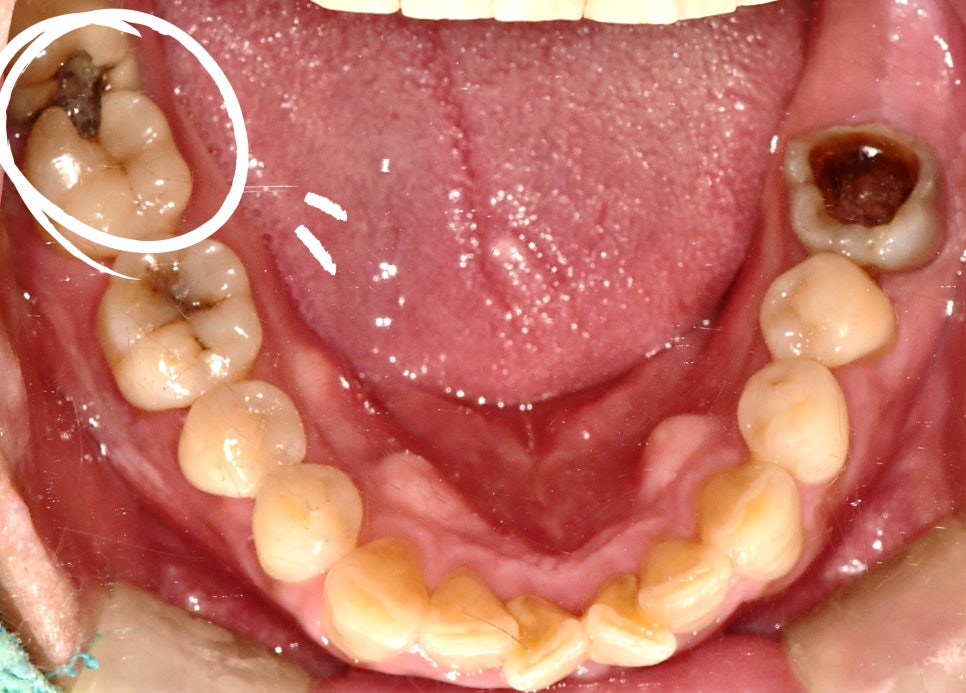

첫 번째 단계는 문제의 원인인 옆으로 누운 사랑니 발치였습니다.

신경과 가까운 까다로운 위치였지만, 정밀 진단을 통해 안전하게 발치를 진행했습니다.

이후 남은 어금니(#47)를 보존하기 위한 치료 계획을 세웠습니다.

현미경 신경치료 & 치관확장술

보통 이런 상황에서는 임플란트를 추천하는 경우가 많습니다.

그러나 정밀검사 결과 치아 보존 가능성이 있다고 판단되어 끝까지 살리기로 했습니다.

✅ 치관확장술

#47은 충치와 잇몸 손상으로 치아 머리 부분이 거의 남지 않아 보철물이 안정적으로 올라가기 어려운 상태

치관확장술을 통해 잇몸 속 치아를 더 드러내 안정적으로 보철을 올릴 수 있는 조건 확보

보철과 전문의와 협진하여 진행